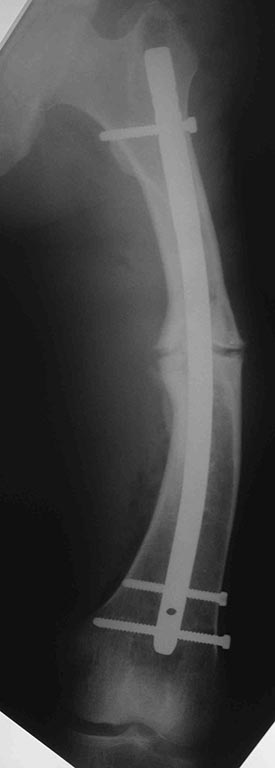

[Ortho] перелом бедра с исходной деформацией

Сегодняшние снимки из операционной, подходящей пластины не было, а

гвоздь был.